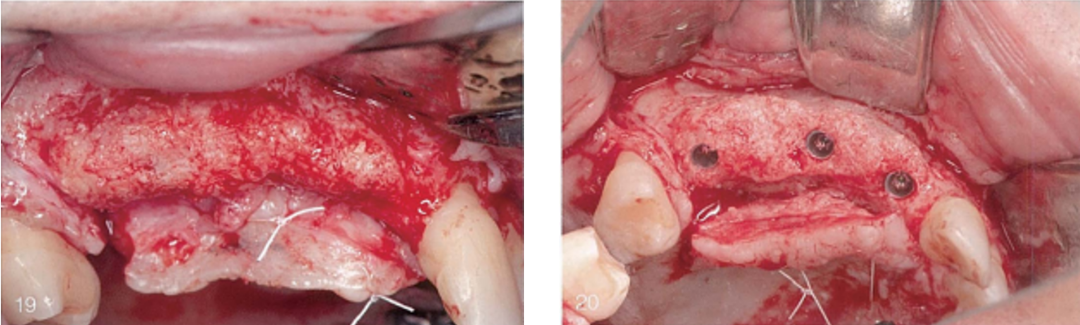

(19)和(20)唇侧观和牙合面观,骨再生最终效果。可见健康的新生骨,垂直骨有最显著增加,宽度上足以植入种植体。但由于术后感染,垂直向骨增量不够充足。